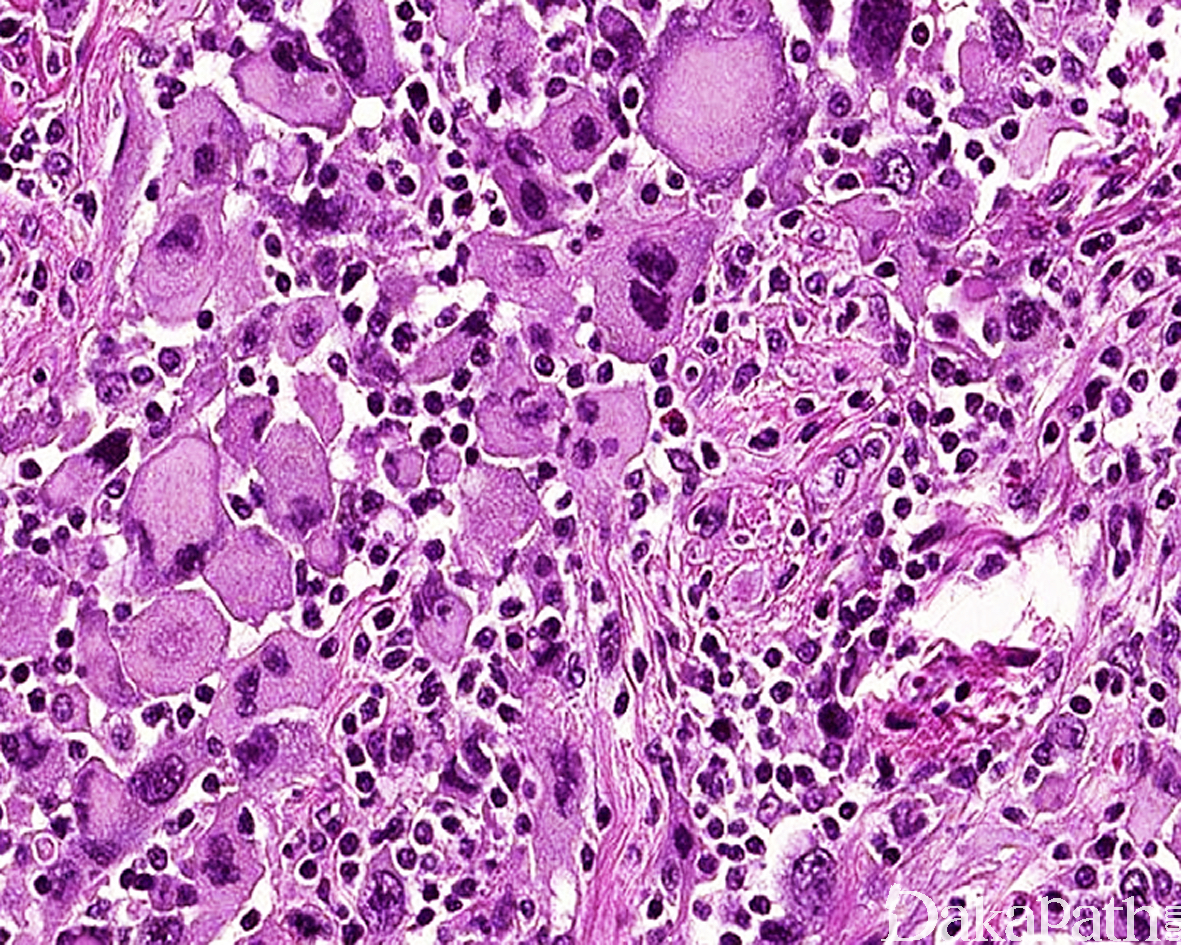

镜下见肿瘤由异型性明显的圆形、多边形深嗜酸性的细胞和一些小的未分化细胞及梭形细胞混合组成;

部分细胞呈蝌蚪状、带状或网球拍状,胞质呈深嗜伊红色,外形不规则,一些细胞大而畸形,具深伊红色胞浆,这类细胞具有诊断价值;

少数病例瘤细胞胞质丰富,因中间丝聚集在核旁而呈包涵体样,核大,圆形和卵圆形,常偏位,染色质空泡状,可见明显的核仁;

部分区域可见瘤巨细胞或多核巨细胞,类似多形性未分化肉瘤;

肿瘤内常见坏死灶,核分裂象活跃。